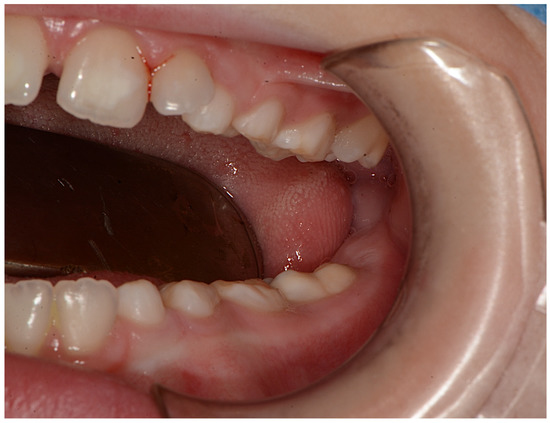

| Present study 2021 | 1 patient | M | high narrow palate, crowding, molar incisor hypomineralization (MIH), second class | 9 |